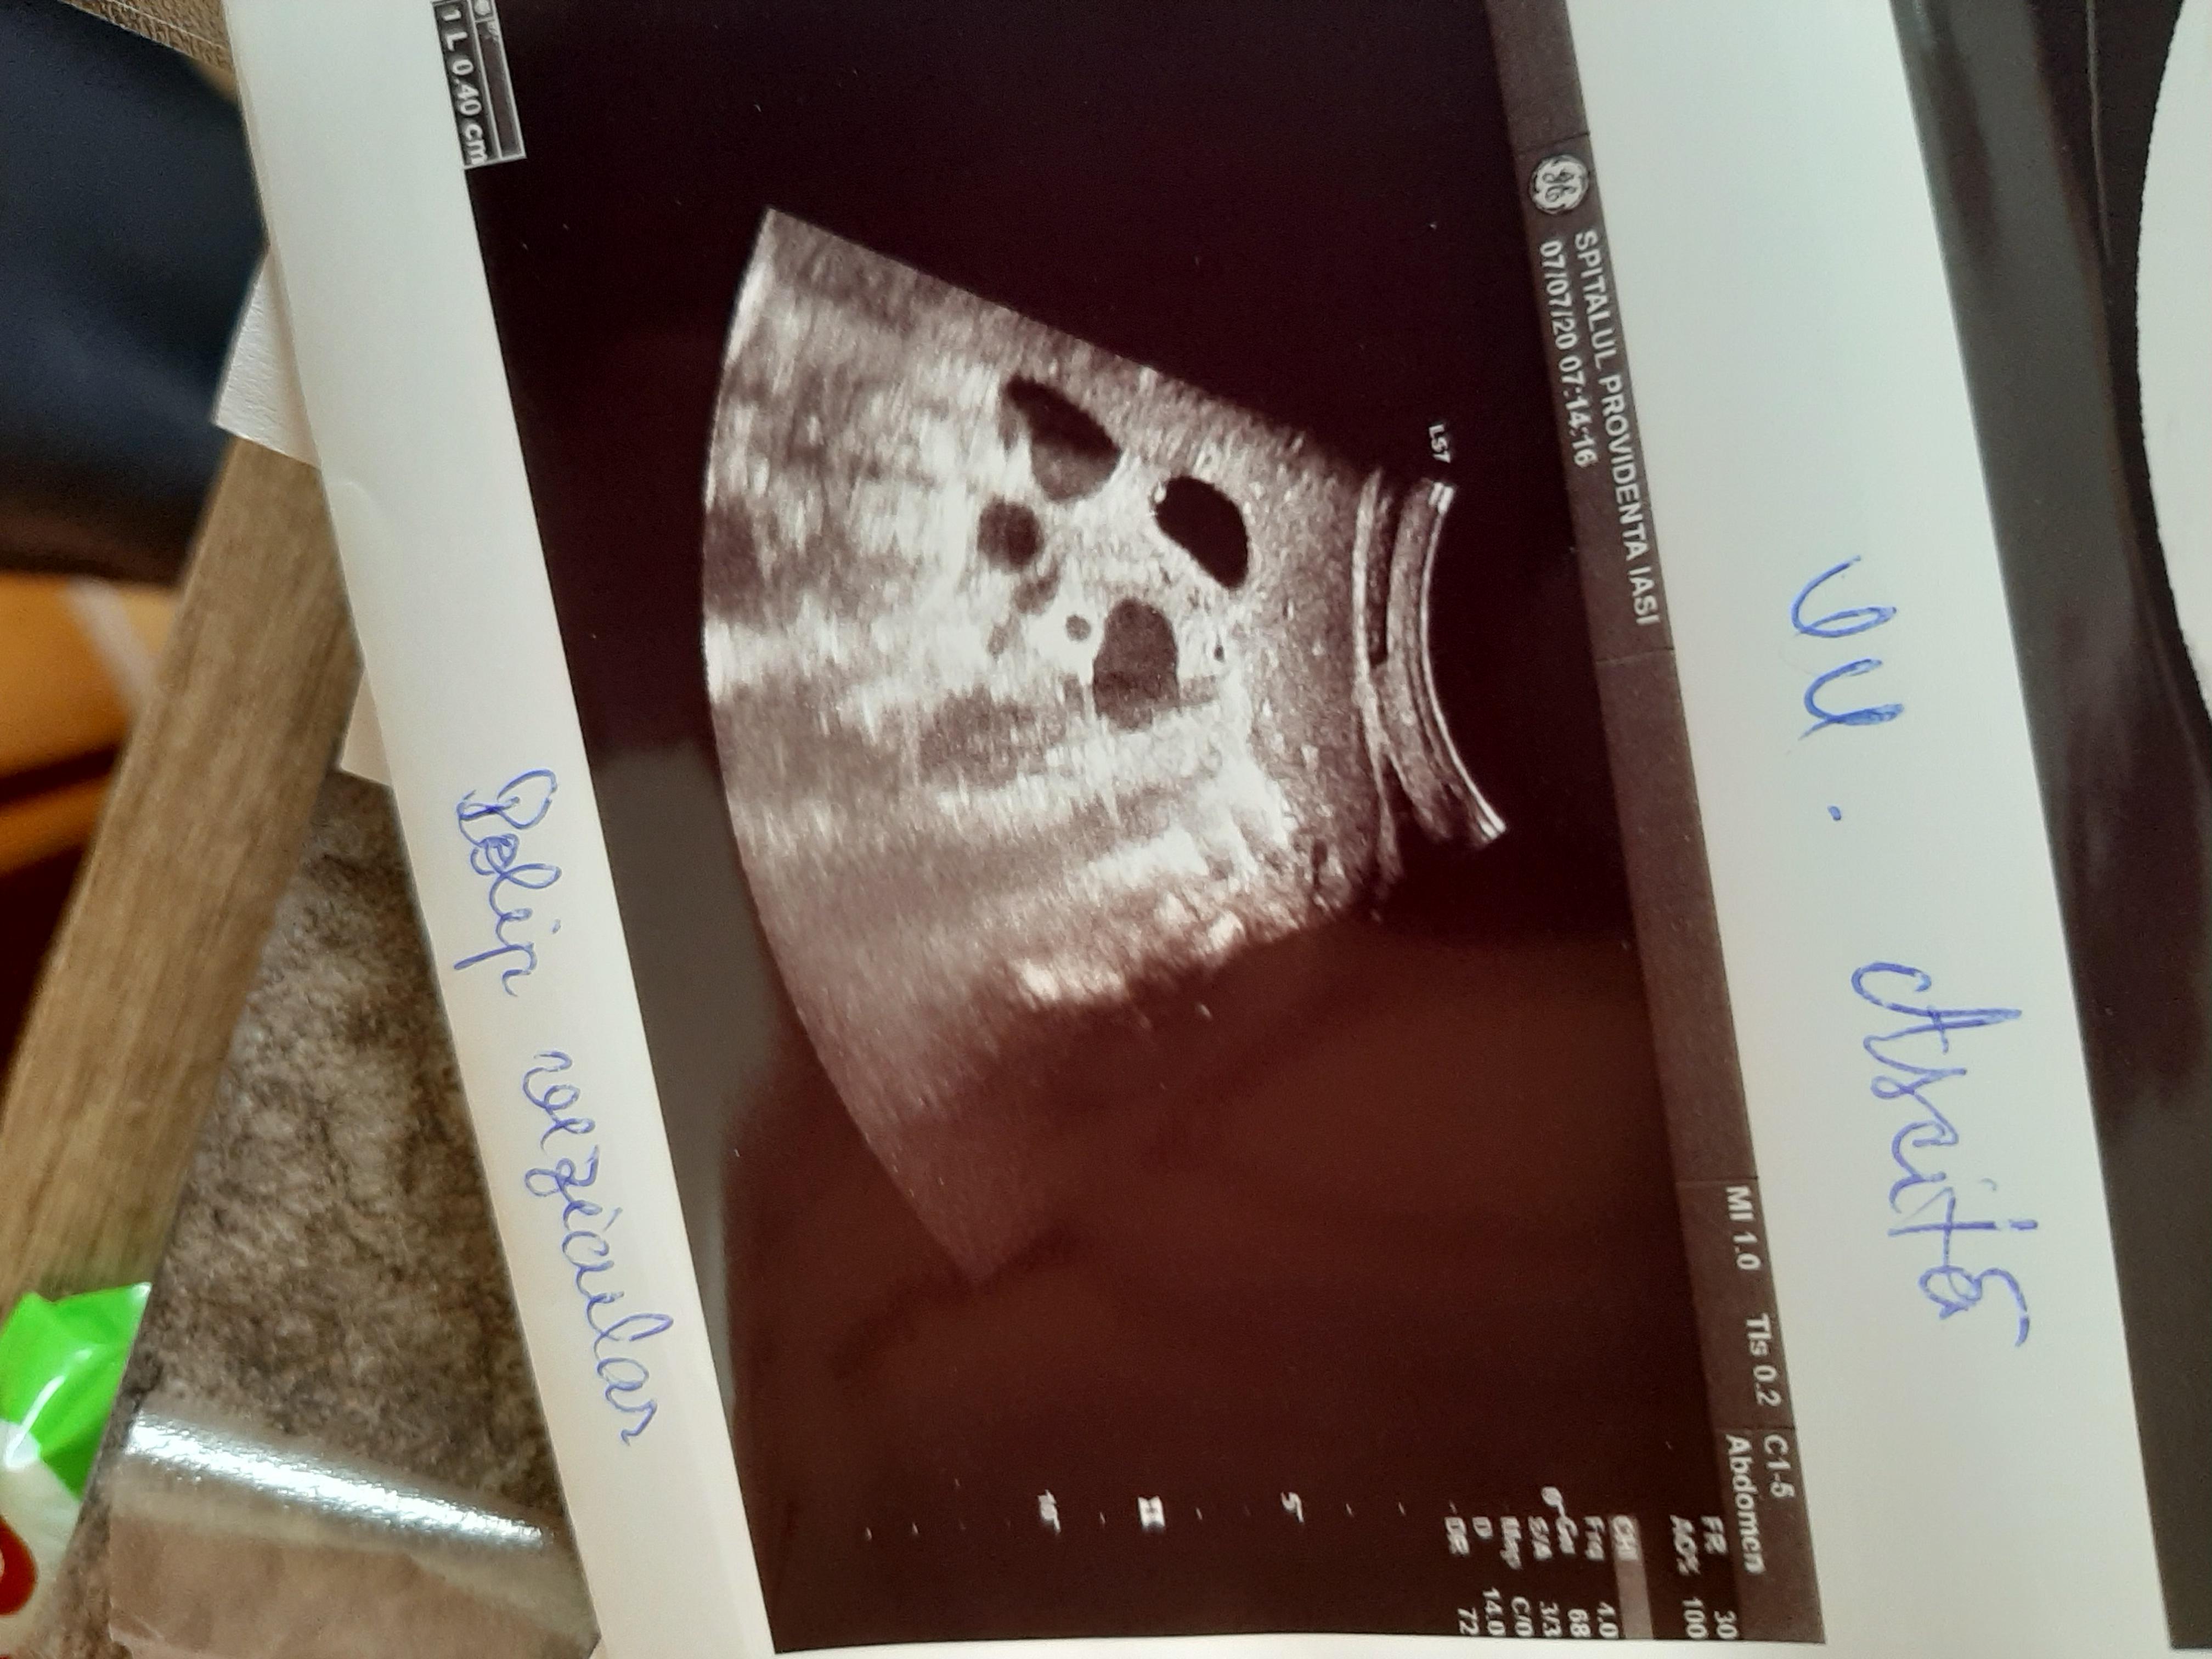

Diagnosticul medicilor a fost: sindrom hipoanabolic, litiază biliară veziculară, boală de reflux gastroesofagian, antecedente de colită repetată cu Clostridium Difficile.